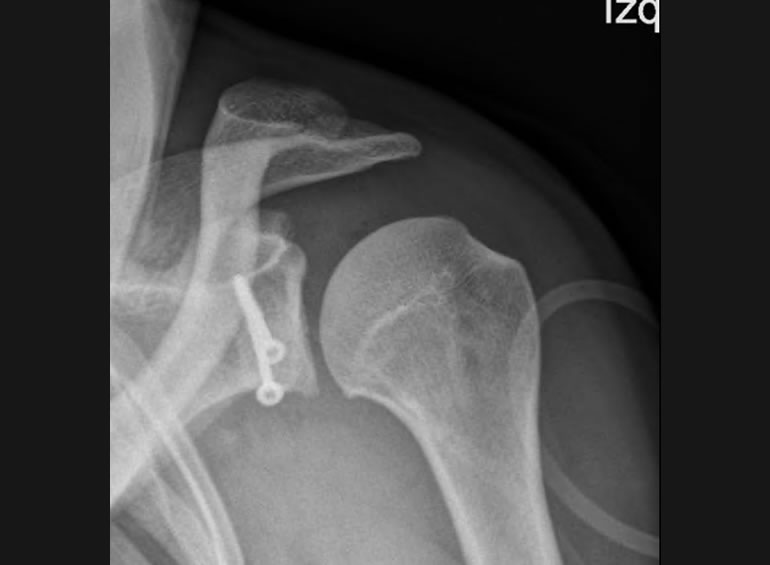

Desde el año 2015, al regresar de mi formación como subespecialista en Francia, estoy 100% dedicado al tratamiento de pacientes con lesiones traumáticas, degenerativas y deportivas de Hombro y Codo. Dividiendo mi practica clínica en pacientes con accidentes o secuelas en el Hospital Clínico Mutual de Seguridad CChC y a pacientes privados con lesiones traumáticas deportivas o domésticas y lesiones degenerativas en Clínica Alemana de Santiago.

Tras un accidente automovilístico de alto impacto con una serie de secuelas físicas, entre ellas la destrucción de mi codo quede con un brazo sin movimiento. Comencé la búsqueda de opiniones médicas para recuperar mi movilidad perdida y soñando volver a hacer algo tan sencillo como tocar mi cara, en esta búsqueda conocí al Dr Reinares quien me dio una esperanza con la cirugía de Protesis de Codo. Me sometí a dicha cirugía en el año 2016 de la que obtuve maravillosos resultados, recupere mi movilidad tan anhelada que me ha permitido hasta el dia de hoy realizar todas las actividades de mi vida diaria, Tremendamente agradecida de este gran profesional